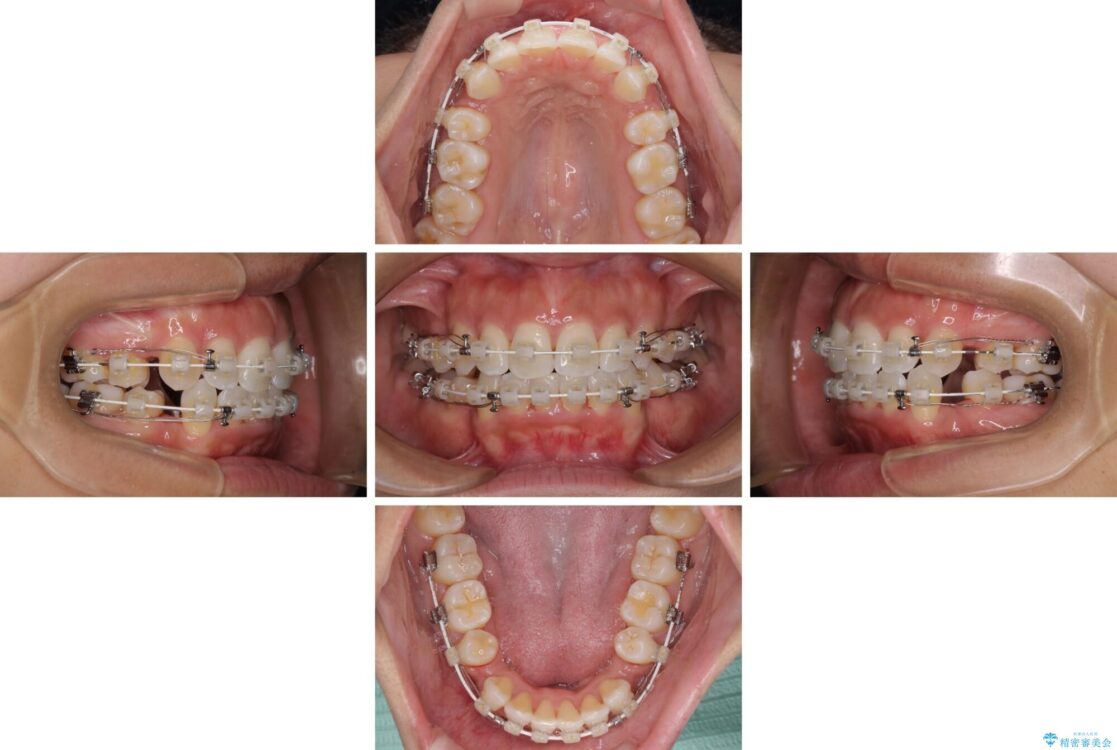

治療途中

• 抜歯矯正で唇を閉じやすく 目立たないワイヤー装置 治療途中画像